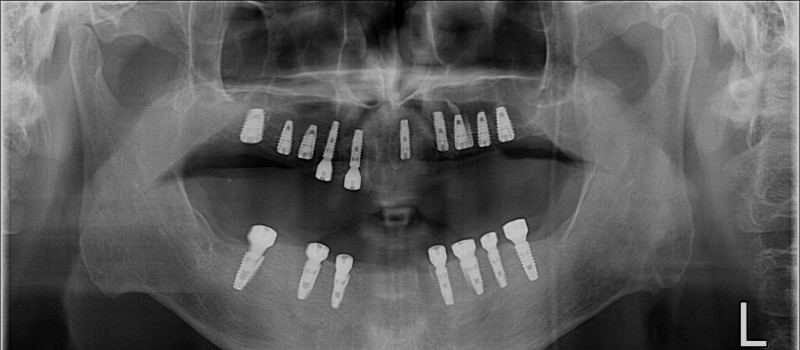

중간과정 ▼